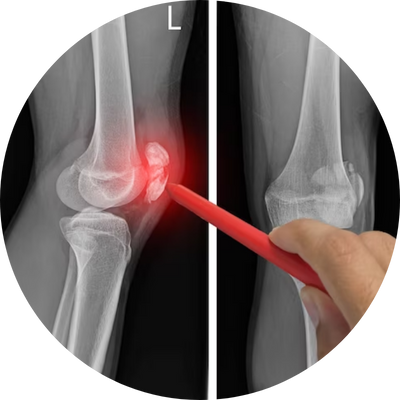

Raio-X do joelho

O raio-X do joelho é um exame de imagem que usa radiação ionizante para avaliar a anatomia interna do joelho. É um exame de primeira linha para avaliar o joelho, principalmente quando há dor persistente na articulação.